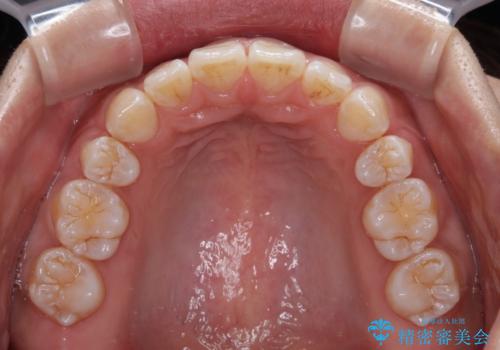

くちばしのような前歯 抜歯矯正で口を閉じやすく

- 前歯の突出感を気にして来院された患者様です。

咬合力が非常に強く、咬合力で前歯が前方に押し広げられており、上下唇に閉じにくさが認められました。

上下左右の第一小臼歯4本を抜歯し、ワイヤー装置にて矯正治療を行うこととしました。

強い咬合力により前歯の隙間がなかなか閉じられず、治療期間は長いものとなりましたが、横顔の印象が大きく変わるほど口元の印象を改善することができました。